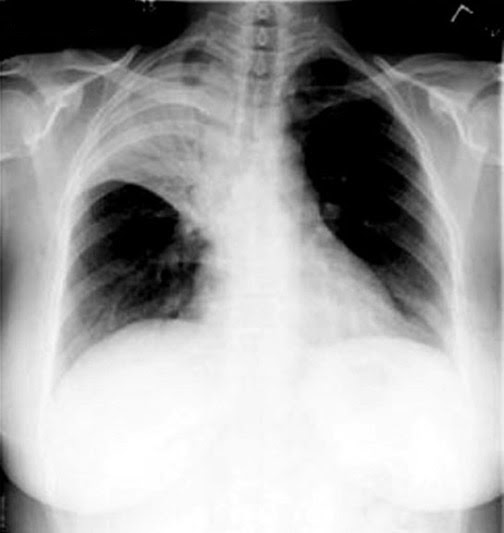

Chest Xray documented right lower pneumonia. Download Scientific Diagram How To Read A Chest X Ray With Pneumonia Blood tests are used to confirm an. In fact every radiologst should be an expert in. The term pneumonia is most commonly used to mean acute infection of the lung parenchyma. Trachea, carina, bronchi and hilar structures. If pneumonia is suspected, your doctor may recommend the following tests: Sometimes chronic infections are included. Doctors typically use this procedure to help. How To Read A Chest X Ray With Pneumonia.